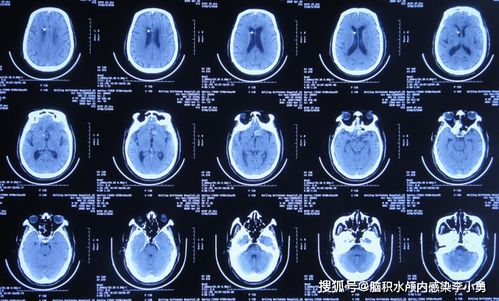

对于这种症状,首先建议完善24小时动态心电图检查,以排除器质性疾病的可能性。通过心理调节和规律作息来改善症状也是非常重要的。必要时,患者可以在医生的指导下使用调节植物神经的药物。